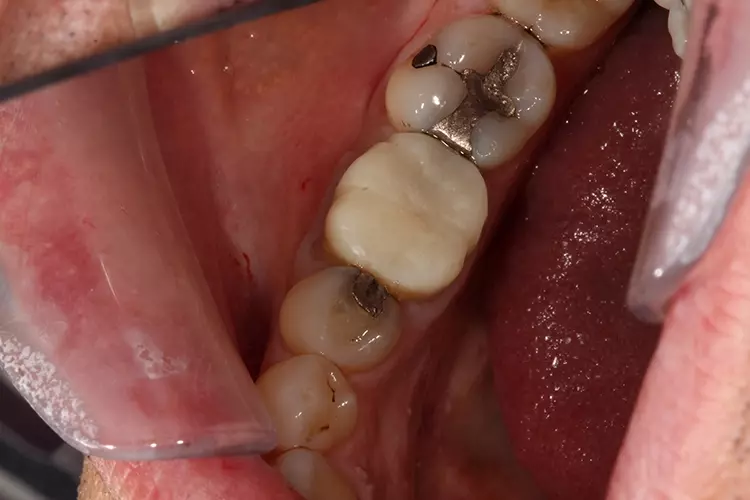

Die klinische Untersuchung zeigte eine klobige Metallkeramikkrone auf Zahn 46. Der Parodontale Screening Index ergab einen Wert von 3 im unteren rechten Sextanten.

Beim Sondieren traten Blutungen auf, die distal von Zahn 46 stärker ausgeprägt waren. Daher wurde an dieser Stelle ein weiteres 6-Punkt-Taschendiagramm erstellt, das Taschen von 4 mm Tiefe auf der distobukkalen Seite von Zahn 46 mit Blutungen zeigte. Zusätzliche Perkussionstests im unteren rechten Quadranten ließen erkennen, dass Zahn 46 nicht auf Perkussion reagierte.

Die Behandlung begann mit dem Auftrennen und der Entfernung der Krone. Anschließend wurde die Sekundärkaries entfernt und der Stumpf mit VisCalor bulk (VOCO) repariert. Hierbei handelt es sich um ein Bulk-Fill-Komposit mit thermisch kontrollierter Viskosität, welches sich gut für Klasse-II-Restaurationen oder Stumpfrekonstruktionen eignet.

Die Krone wurde mit einem konischen Diamantschleifer mit flachem Kopf (Frank Dental) aufgetrennt. Kariöses Gewebe wurde mit einem zylindrischen Diamantbohrer (835.010C, NTI) und einem Rosenbohrer (1204025RA, Edenta) entfernt.

Die Präparation für die neue Krone erfolgte mit konischen Fräsern grober und mittlerer Körnung (850.014C/M, Solo Diamond). Nach der Kariesentfernung war eine Anhebung der tief liegenden Kavitätenränder erforderlich, die ebenso wie auch der Aufbau des restlichen Stumpfes mit VisCalor bulk (VOCO) erfolgte. Um eine Weichgewebskonditionierung zu ermöglichen, wurde eine provisorische Krone hergestellt, die der Patient vor der digitalen Abformung einige Wochen getragen hat (Abb. 2a und 2b).